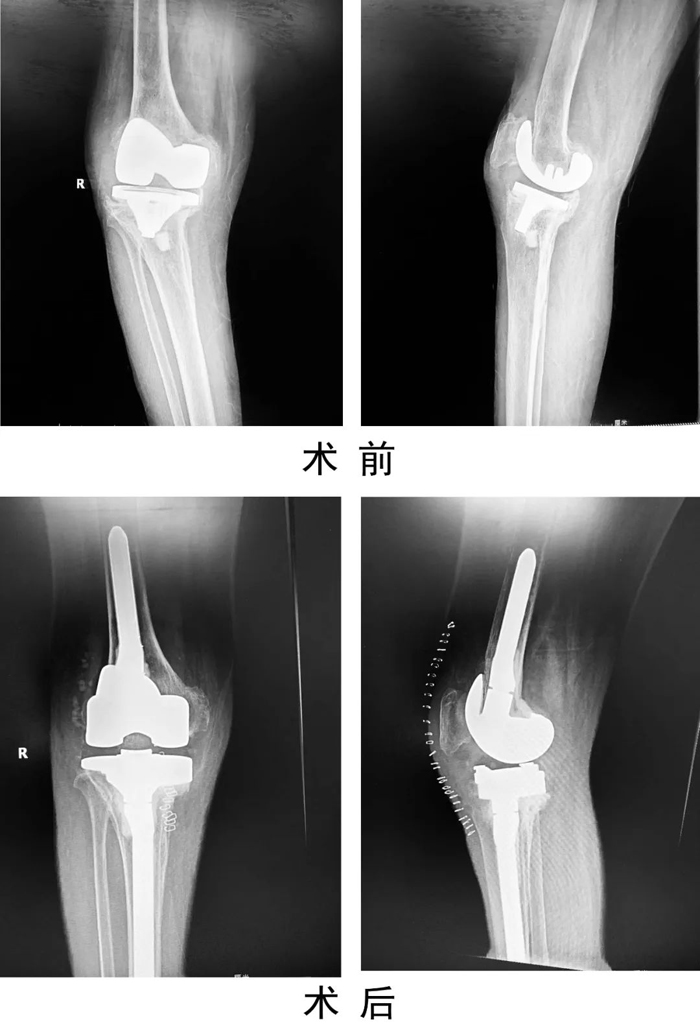

患者,女,69歲,因“右膝人工關(guān)節(jié)置換術(shù)后6年,疼痛伴活動(dòng)受限1年”入住關(guān)節(jié)運(yùn)動(dòng)醫(yī)學(xué)二科。術(shù)前X線示右膝人工關(guān)節(jié)假體松動(dòng),感染指標(biāo)檢查:C反應(yīng)蛋白80mg/L,血沉20mm/h,關(guān)節(jié)穿刺培養(yǎng)提示表皮葡萄球菌感染。查體見有膝部有一長(zhǎng)約15cm手術(shù)疤痕,皮溫高,關(guān)節(jié)腫脹,右膝關(guān)節(jié)活動(dòng)受限。入院診斷為:右膝關(guān)節(jié)假體周圍感染,人工假體松動(dòng),右脛骨平臺(tái)骨缺損。

患者入院后,關(guān)節(jié)運(yùn)動(dòng)醫(yī)學(xué)二科手術(shù)團(tuán)隊(duì)制定嚴(yán)密的手術(shù)計(jì)劃,為患者實(shí)施了一期右膝人工關(guān)節(jié)翻修術(shù),一次手術(shù)清除原假體,徹底清創(chuàng)后,重新植入翻修假體。手術(shù)后患者右膝刀口一期愈合出院,患膝功能良好,疼痛緩解。復(fù)查感染指標(biāo)C反應(yīng)蛋白4.45mg/L。